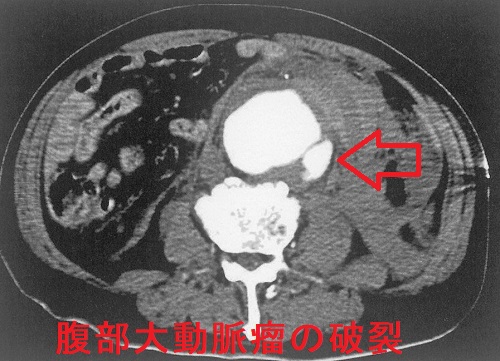

腹部大動脈瘤(AAA)からの動脈性出血では出血性ショックに至ります。鑑別を要する病気のほとんどが痛みのために血圧が上昇しますが、腹部大動脈瘤破裂は、逆に血圧が低下し、急激な貧血の進行を伴うショックバイタルになります(ここで気付けば上等)。

腹部大動脈瘤破裂が始まれば致死率は80-90%になります。

腹部大動脈瘤(AAA)があれば、周囲の動脈、特に腸骨動脈にも同じような動脈瘤が存在する可能性があります。これらはステントを留置するカテーテル手術の適応となります。